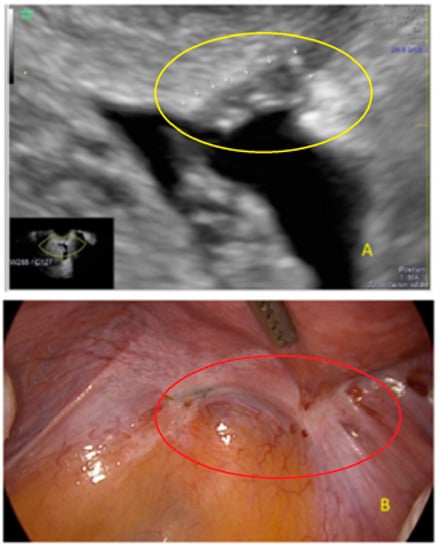

- The lesion may be convex, protruding from the peritoneal surface into the peritoneal cavity (we called this “bulging”), or it may appear as a concave defect in the peritoneum (we called this a “pocket”).

- The presence of hyperechoic foci (we called this a “pearl”).

3.1. Cystic Solitary Lesion